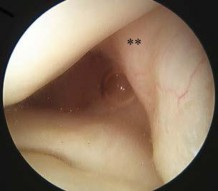

Question 9:

A 22-year-old female soccer player sustains a twisting injury to her left knee. An AP radiograph demonstrates a small vertical avulsion fracture of the lateral tibial plateau, distal to the joint line. This fracture is considered pathognomonic for an injury to which of the following structures?

Correct Answer: Anterior cruciate ligament

Explanation:

The radiograph describes a Segond fracture, which is an avulsion fracture of the anterolateral aspect of the proximal tibia. It is typically associated with avulsion of the anterolateral ligament (ALL) or lateral capsular attachments and is highly predictive (pathognomonic) of an anterior cruciate ligament (ACL) tear.